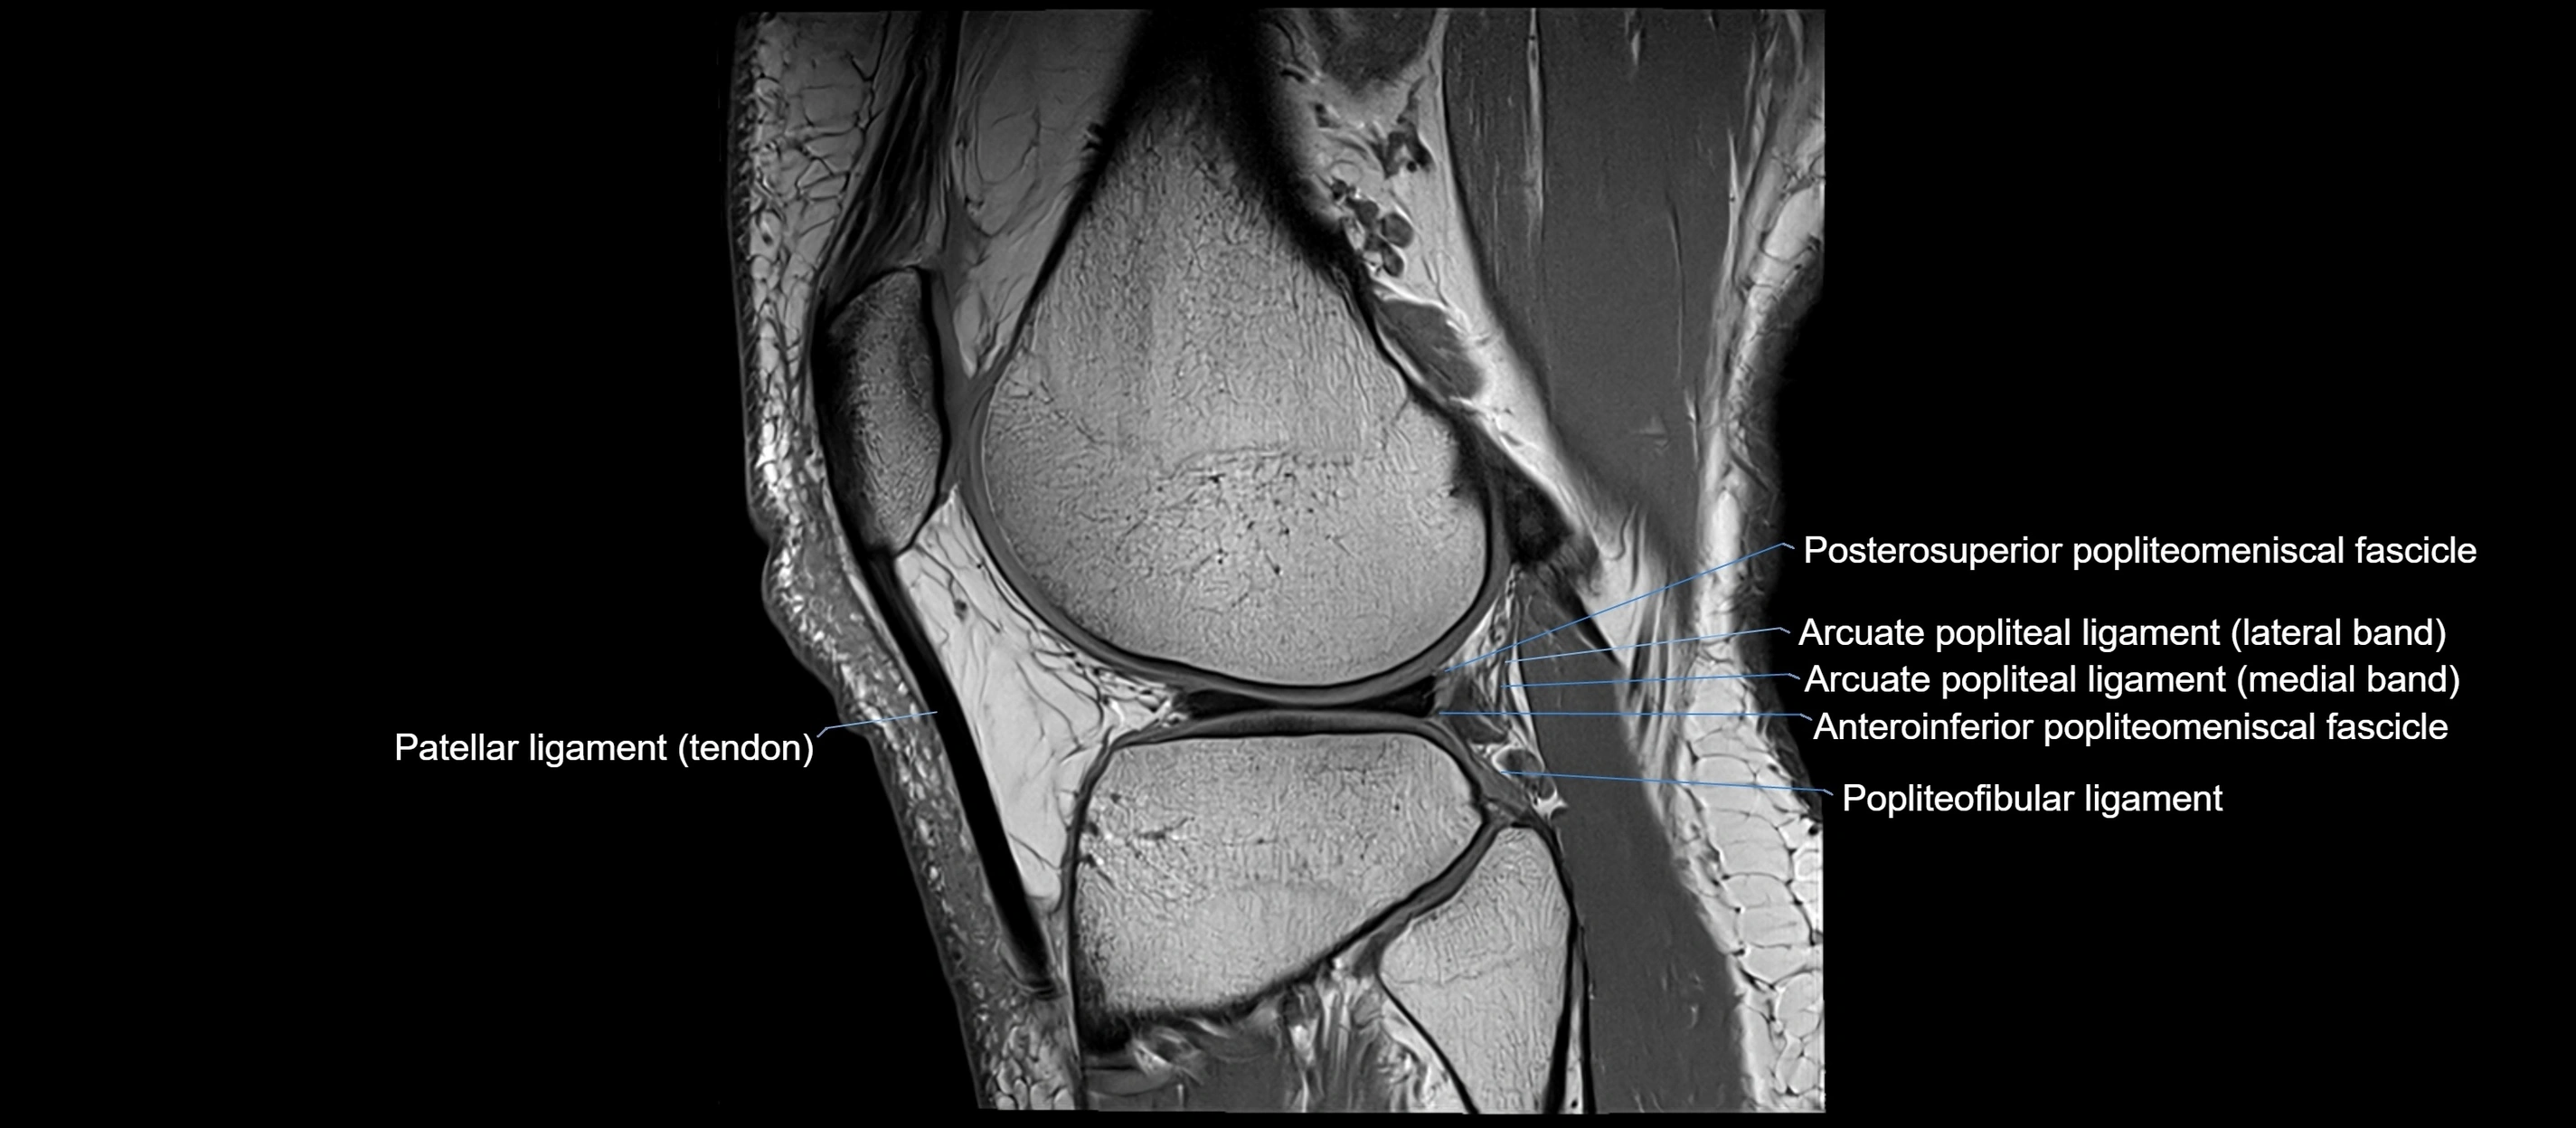

MRI images

image